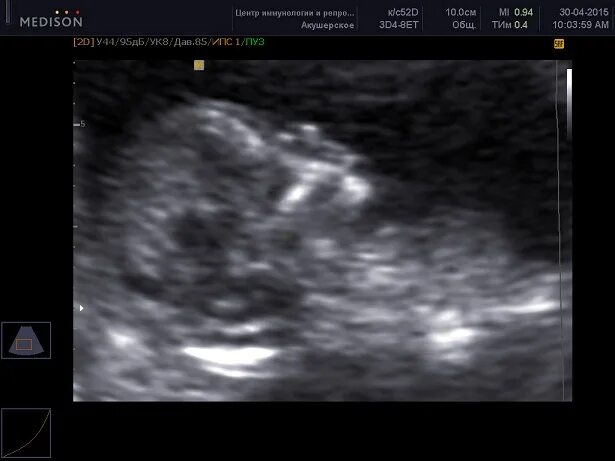

Синдром дауна 2 триместра